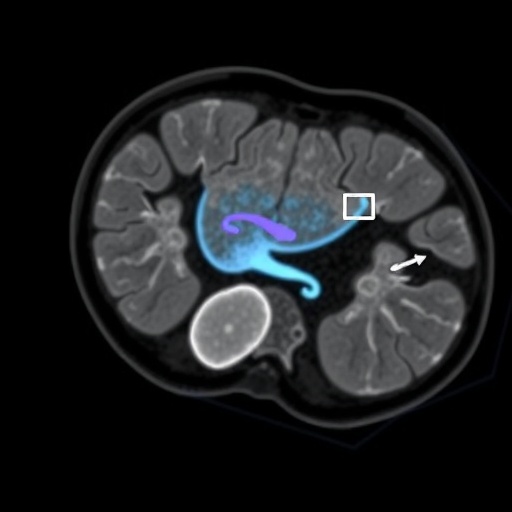

In the study conducted by Baltacioglu and colleagues, researchers aimed to compare the diagnostic accuracy of the whole abdomen FDG PET/MRI with standard whole body PET/CT scans specifically for assessing peritoneal recurrence. The incorporation of MRI not only allows for detailed imaging of soft tissues but, when coupled with functional PET data, gives insight into metabolic activities of tumors. This fusion of anatomical and metabolic imaging technologies is revolutionary, as it could enable healthcare professionals to visualize and characterize peritoneal lesions more effectively.

The study utilized a cohort of ovarian cancer patients who were previously treated and were under surveillance for possible recurrence. Participants underwent both imaging techniques, and the results were meticulously analyzed to ascertain which modality provided superior detection rates of peritoneal metastases. The findings indicated that whole abdomen FDG PET/MRI significantly outperformed standard PET/CT, highlighting the benefits of MRI’s high-resolution imaging capabilities in revealing small and subtle lesions that might otherwise be missed.

Furthermore, the metabolic information provided by FDG PET enhances the specificity of lesions detected through MRI. The study posited that the metabolic activity of peritoneal lesions could correlate strongly with the biological aggressiveness of the tumors. As such, the integration of PET with MRI not only improves the likelihood of detecting cancer recurrence but also aids in refining treatment planning and potentially prognostic assessments of patients.